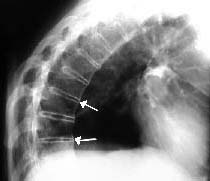

Sindesmofito marginal: es un puente delgado, dispuesto verticalmente que se origina en la inserción del anillo fibroso comprometiendo las vértebras adyacentes, correspondiente a la calcificación de las capas periféricas del anulus y que puede comprometer el ligamento longitudinal anterior. Radiológicamente se visualiza como una calcificación dispuesta entre las esquinas de dos vértebras adyacentes (Figura 1).

Figura 1. Paciente con Espondilitis anquilosante. Radiografía de columna dorsal,

vista lateral. Obsérvense los sindesmofitos marginales a lo largo de la columna,

formando puentes entre un cuerpo vertebral y otro (Flechas).